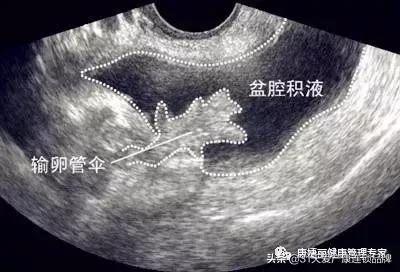

盆腔积液是指对盆腔内液体这一表现的一种描述。可分为生理性盆腔积液和病理性盆腔积液。先来说说生理性盆腔积液。

盆腔处于腹腔最低部,当盆腹腔脏器有少量渗出液、漏出液时,液体会先聚积在盆腔,从而形成盆腔积液。

月经时,少量经血逆流至盆腔可造成盆腔积液;月经中期排卵时的卵泡液积在盆腔也可导致盆腔积液;便秘的患者,由于肠蠕动不正常,可引起少量肠液渗出导致盆腔积液。